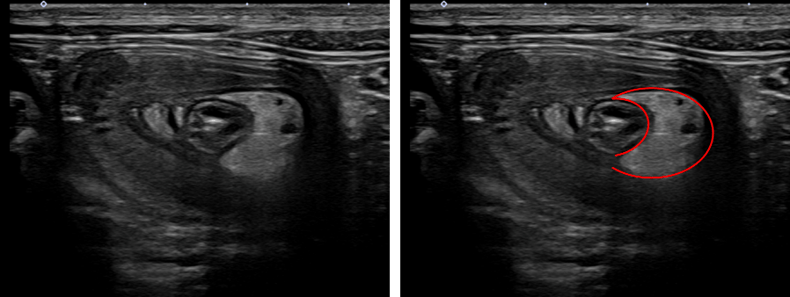

エコー検査では右上腹部に、crescent-in-doghnut signとその周囲のリンパ節の腫れがみられました。crescent-in-doghnut signとはターゲットサインの一種で、腸が腸の中に入り込んでいる様子が、あたかもドーナツの中にかけた三日月が入り込んでいるように観察されるためこう呼ばれます。

↑crescent-in-doghnut sign